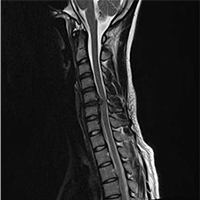

• 정상 경추 MRI

• 경추 5/6 추간판탈출증

(디스크)